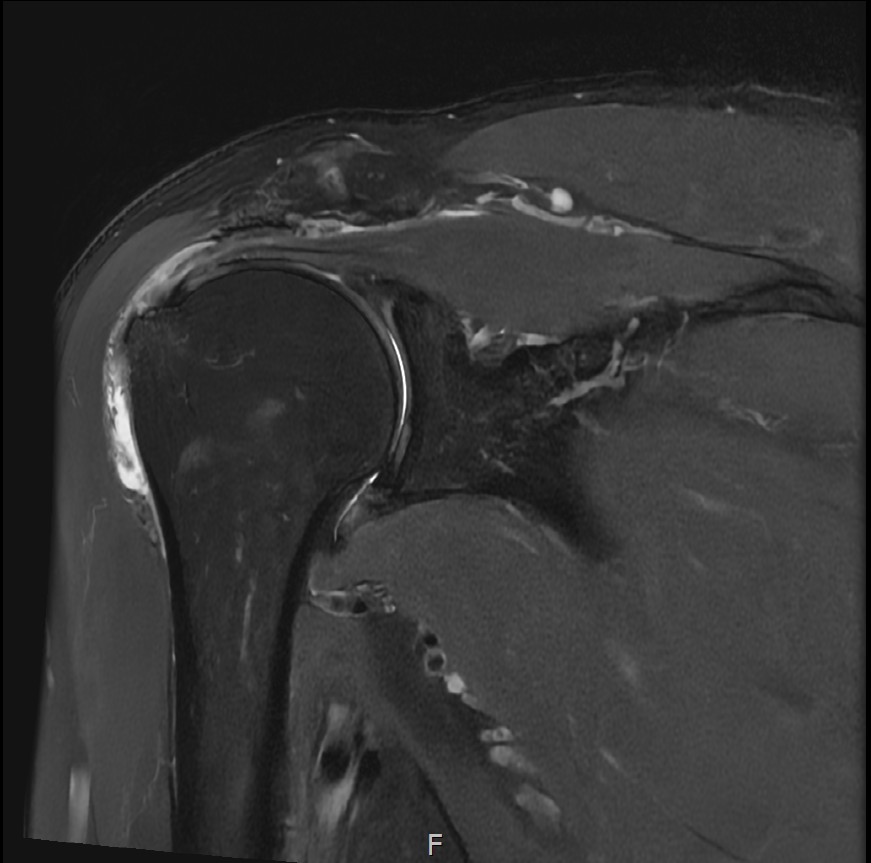

MRI를 검토해보았습니다.

회전근개 극상건의 점액낭면측(bursal-side) 부분파열. 처음보다 파열 범위가 약간 넓어져 있었고, 인대가 얇아진 소견도 보였습니다.

점액낭면측(bursal-side) 파열은 회전근개의 위쪽, 즉 점액낭에 면한 부분(외측)이 손상된 것입니다.

MRI: 극상건 점액낭면측 부분파열

인대 두께: 4.2mm (정상 5~6mm보다 얇음)